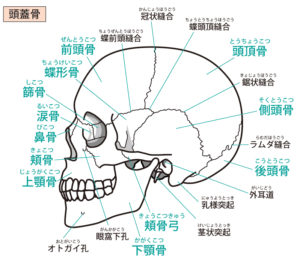

そしてその恥骨部は頭のこめかみ部分(蝶形骨)と連動していますので、歪みが大きいと生理で骨盤が動くときに頭痛や目のトラブルの原因になります。

このこめかみの骨(蝶形骨)は目の裏で左右が繋がっている骨なので目に対する影響もありますが、他に体中の関節の動き、手先足先、内臓、呼吸器系、頚椎など色々と関係していて影響します。